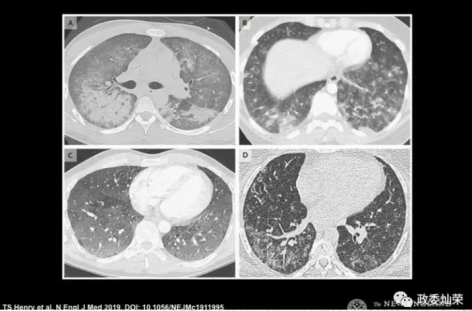

2019年8月19,美国“科学警报网”发布一则新闻称近期出现了100例神秘肺病,它们可能与“电子烟”相关。如果结合前面马里兰州生化武器基地关闭的话,事实上这些病例极有可能是第一批感染“新冠肺炎”的患者!

美国肺病x光片.png

2019年8月25日,“华盛顿邮报”发布新闻称全美22州至少已经有193例“神秘肺炎”患者。(笔者注:原链接已无法访问,疑似被删除)

2020年2月25日,美国疾控中心做了关于“神秘肺炎”的总结。该肺炎被命名为“EVALI”,疾控中心认为其主要是由电子烟中的醋酸维生素E引起的。疾控中心称“EVALI”从2019年8月、9月爆发之后病例逐渐减少,所以此次发布为最后一次对全国患者数及死亡人数的更新。截止2020年2月18号,共住院治疗2807例,其中死亡68例。然而事实真如美国疾控中心所说“神秘肺炎”只是由电子烟中的醋酸维生素E引起的吗?

根据美国疾控中心的研究数据,在867例“EVALI”患者,有86%吸含THC成分的电子烟,64%吸含有尼古丁成分的;34%只吸含THC成分的,11%只吸含尼古丁成分的(注:THC电子烟中含有50%的醋酸维生素E)但这组数据根本不能证明醋酸维生素E是“神秘肺炎”的致病原因。

美国肺病x光片解说.png

况且最为关键的一点是THC电子烟在市面上已经出售多年,且不止在美国出售,为什么早不出现,晚不出出现,偏偏出现在美国生化实验室关闭后,武汉爆发“新冠肺炎”之前?